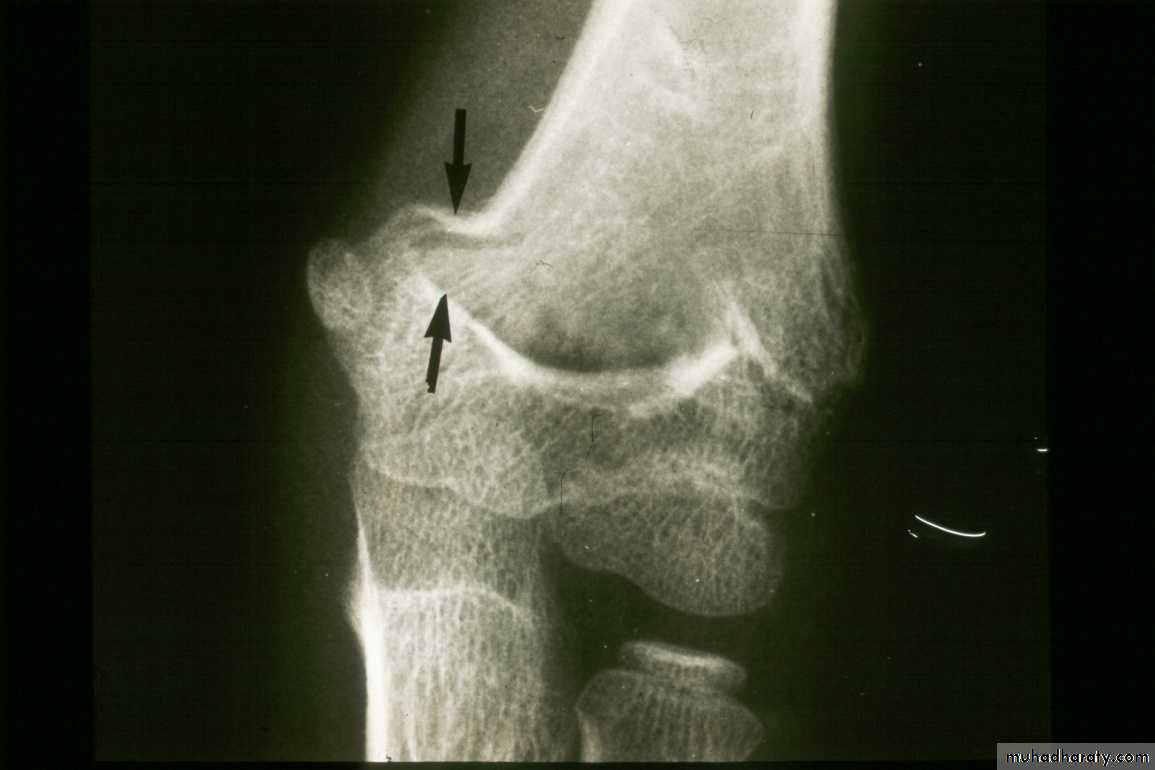

What are the criteria for Type I Fractures ?

Absence of

a crescent sign

If there was no definite fracture

seen on the injury films,what confirms the presence

of a suspected Type I fracture?

Injury film

3 wks post fracture

fat pads displaced

Type I suspectedPeriosteal new bone

The original suspicions of

a fracture are now confirmed.

What are the two major displacement deformities occurring in Type I injuries ?

1. Medial greenstick collapse

2. Hyperextension of the condyles

This can accentuate the varus.

A more careful evaluationof our original “undisplaced” fracture

reveals both deformities were present

on the original x-rays.

Medial greenstick collapse

+Distal hyperextension

The crescent sign

indicates a varus alignment.